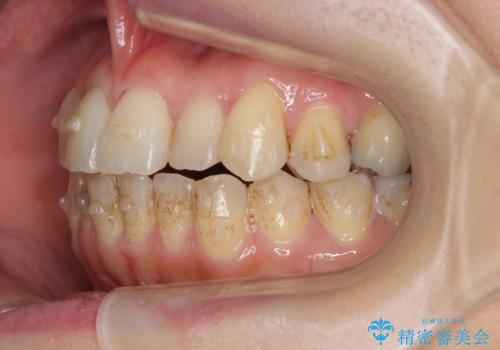

- 前歯のガタガタを主訴に来院。

前歯は開咬傾向であり、小臼歯から大臼歯にかけてもオーバージェットは非常に小さく咬耗していました。

非抜歯で前歯の重なりを作るのは難しいとご説明しましたが、インビザラインでできるところまで並べていくことになりました。

途中再評価を行い、矯正用のミニスクリューを用いて奥歯を遠心移動し、前歯の出っ歯傾向を改善しました。

左上12の段差についてはここまで直すのにもかなり時間がかかりました。インビザライン単独では限界があると説明し、ワイヤーの部分矯正もご提案しましたが、患者様のご希望によりインビザラインでできるところまで頑張るということで4回ほどリファインメントを行いました。